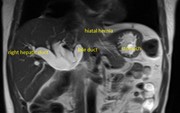

Massive hiatus hernia complicated by jaundice

Ruelan V. Furtado and others

Journal of Surgical Case Reports, Volume 2015, Issue 7, July 2015, rjv087, https://doi.org/10.1093/jscr/rjv087